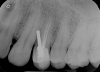

Fig 1. Root perforation caused by improper preparation and placement of an oversized post (dentistry courtesy of Riccardo Tonini, MD, DDS).

Figure 1

Furthermore, the reconstruction of endodontically treated teeth can present restorative and esthetic challenges for the technician and clinician.23 The failure of these post-retained systems has been documented in numerous clinical studies.10,13,21,24-29 Many of these studies indicate that the failure rate of restorations on pulpless teeth with posts and cores is higher than that for restorations of vital teeth because of their structural differences and the significant loss of tissue.30-35 Several main causes of failure of post-retained restorations have been identified, including recurrent caries, endodontic failure, periodontal disease, post dislodgment, cement failure, post-core separation, crown-core separation, loss of post retention, core fracture, loss of crown retention, post distortion, post fracture, tooth fracture, root perforation (Figure 1), improper post placement (Figure 2), and root fracture.11,36,37Also, corrosion of metal posts has been proposed as a cause of root fracture.38 A post and core system fabricated with dissimilar metals can cause galvanic corrosion that occurs between the two dissimilar materials.39 This gradual destructive process involves the electrical interaction of at least two different metals or nonmetallic conductors in an environment (ie, microleakage) that accelerates the corrosion of at least one of them, while the least noble metal corrodes the most.